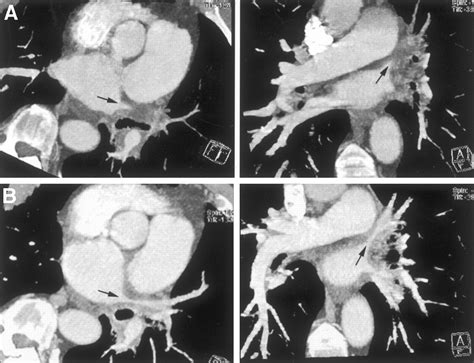

• Imaging Tests: Various imaging tests can help visualize the pulmonary veins and detect any narrowing or blockages. These tests may include:

Computed Tomography (CT) Scan Provides detailed images of the pulmonary veins and surrounding structures, helping to identify the location and extent of stenosis.

These diagnostic tests help healthcare providers determine the presence and severity of Pulmonary Vein Stenosis, guiding the development of an appropriate treatment plan.